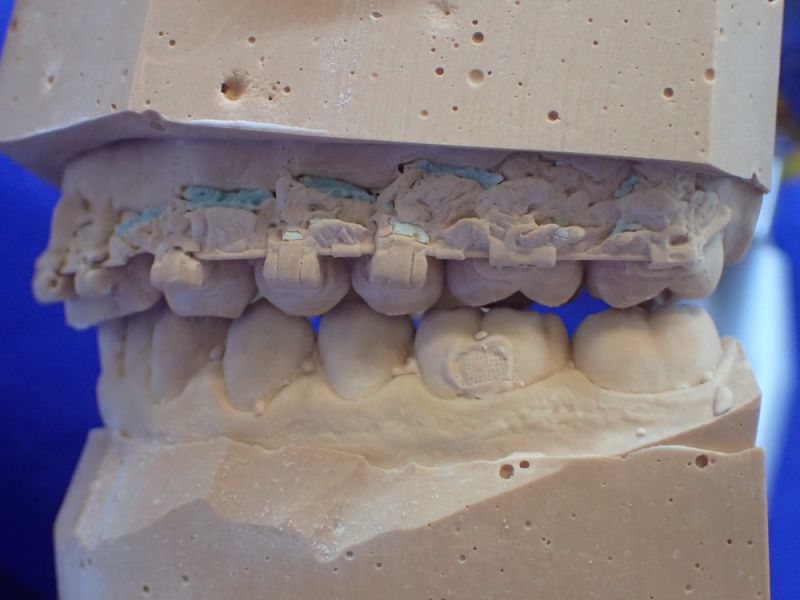

Es erfolgt dieErstuntersuchung und die Herstellung und Eingliederung eines adjustierten Aufbissbehelfs zum Nachweis einer CMD.